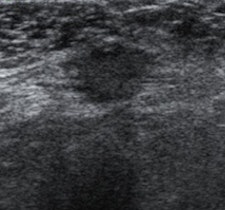

The common ultrasound features were irregular shape, uncircumscribed margins, and hypoechoic masses with intratumoral vascularities. The most common location was within the deep muscle layer, Lee and colleagues wrote.

"When a nodule was oval-shaped, circumscribed marginated, isoechoic, or mildly hypoechoic without any intratumoral vascularity, it was classified as a probably benign finding, corresponding to BI-RADS category 3," they wrote. "We considered rounded nodules or focal nodules with not-circumscribed margins or with any intratumoral vascularity on color power Doppler US as BI-RADS category 4."